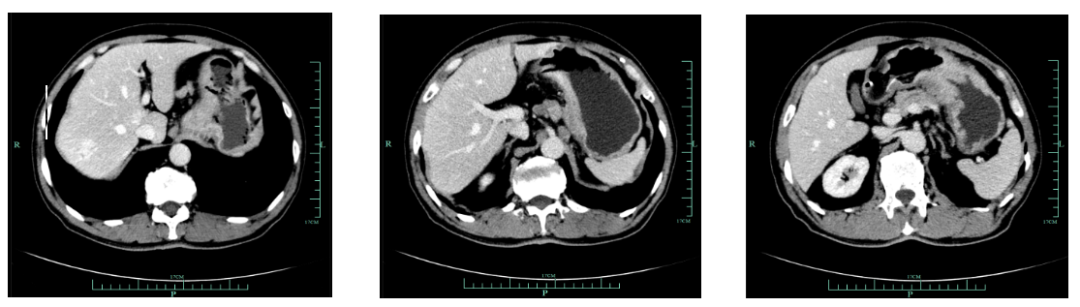

现病史:1月余前出现吞咽哽噎,无饮水呛咳,偶感腹胀腹痛,无恶心呕吐等不适,至外院就诊,上腹部增强CT(2018-12-14)提示:胃小弯及贲门壁异常,提示胃癌。胃周多发肿大淋巴结转移考虑。

既往史(续):全腹部CT平扫+增强提示胃贲门部及体部胃壁增厚,结合临床考虑胃癌伴胃周及腹膜后多发淋巴结转移;肝脏多发血管瘤。

入我院后全面进行评估(2019.4):全腹部CT平扫+增强评估提示腹膜后,胰腺周围多发淋巴结增大,淋巴结转移考虑。